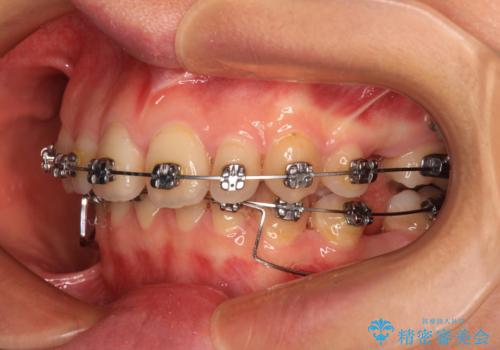

- メタルブラケット

乳歯を残し、欠損部位のスペースを適正な幅に拡大し、インプラント補綴治療により歯列を整える治療も考えられましたが、ご本人から飛び出している前歯をどうしても引っ込めたいとの要望があったため、残存乳歯ならびに上顎左右第二小臼歯を抜歯して、歯列を整えることとしました。

上下臼歯の咬み合わせ改善には補助装置を、深い咬み合わせ改善にはユーティリティーアーチを活用し、ワイヤー装置にて矯正治療を行うこととしました。